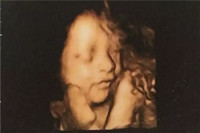

懷孕六個(gè)月男胎兒有多大,懷孕六個(gè)月按孕周期來(lái)計(jì)算的話(huà),即是懷孕21周-懷孕24周,此時(shí)的胎兒體重開(kāi)始大幅度的增加,看上去已經(jīng)很象小寶寶的樣子了,不過(guò)皮膚依然是皺的,紅紅的,樣子像閱讀全文>>

六個(gè)月的胎兒長(zhǎng)成什么樣子,他在四肢,五官,胎長(zhǎng)方面都增長(zhǎng)了多少呢?還有懷孕進(jìn)入六個(gè)月時(shí),孕婦會(huì)里而感覺(jué)便秘,腰酸背痛的情況,其實(shí)那是你沒(méi)有遵守此階段的注意事項(xiàng)。如果你還不...閱讀全文>>